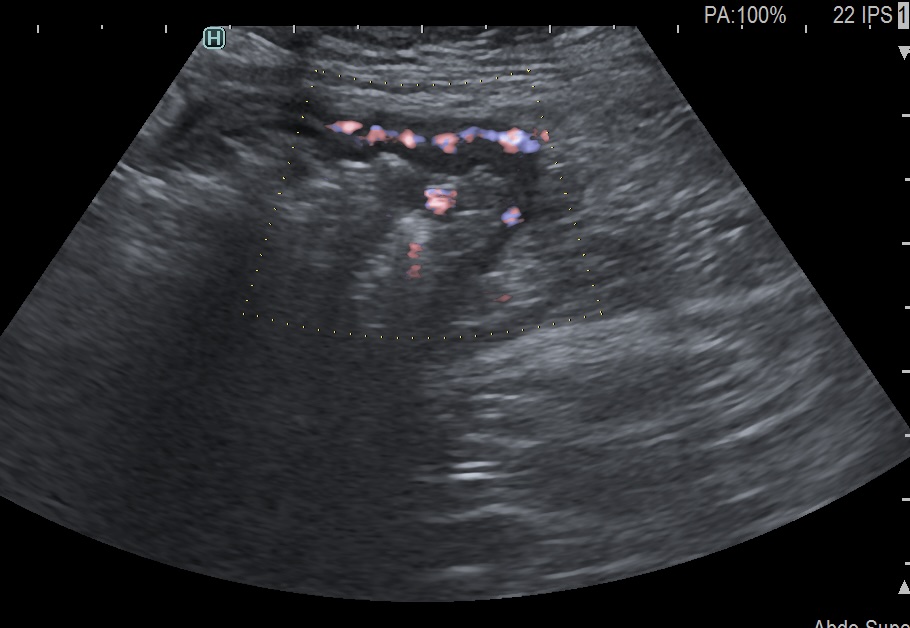

Activité Doppler intense de la paroi et de la graisse

Maladie de Crohn intense activité Doppler paroi et graisse

- Limberg 3 signal abondant dans la paroi et la graisse mésentèrique vascularisation marquée (= Inflammation sévère)